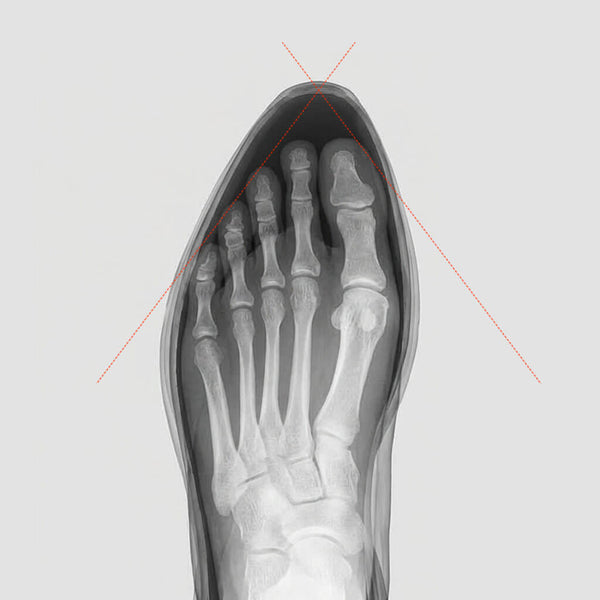

The Narrow Toe Box Problem

Your foot is widest at the toes. Most shoes are not. A tapered toe box squeezes all five toes together, suppresses the natural splay of your big toe — your primary balance anchor — and deforms the forefoot over time. Research links prolonged use of narrow-toed footwear to bunions, hammer toes, and neuromas.